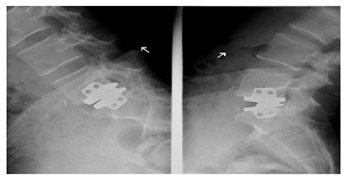

Prothèses discales